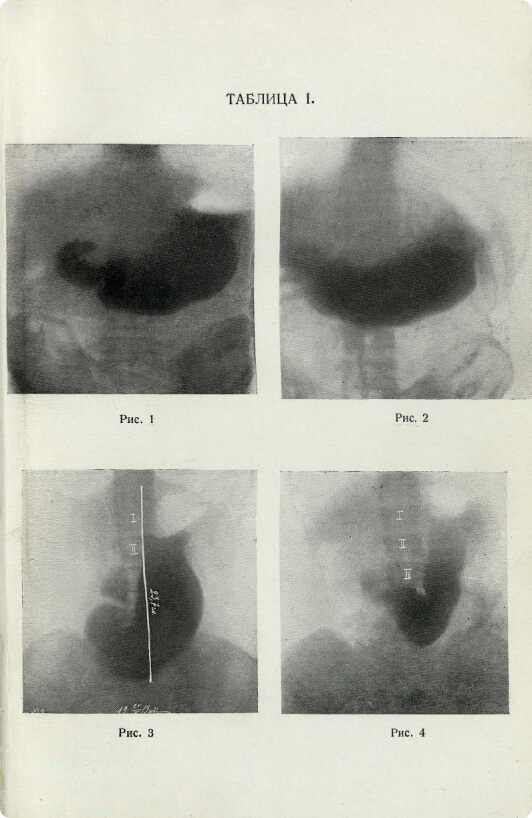

Константин Вячеславович Ипатов,

«Рентгенодиагностика болезней желудка»

К 1910-м годам рентгеновские аппараты стали чаще появляться в клиниках – и тем самым положили начало истории медицинской визуализации, в каком-то смысле став предками и прообразами современных томографов. Руководства по использованию рентгена стали носить не теоретический, а прикладной характер – примером служит детальная брошюра 1912 года издания.

К. В. Ипатов

Рентгенодиагностика болезней желудка

1914, Москва